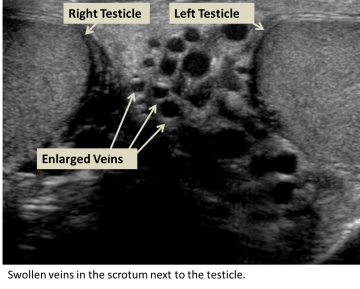

The physician will perform a physical exam, but if the varicocele is small, it can be difficult to see or feel. During the exam, you will be asked to stand and hold your breath while bearing down, also known as the Valsalva maneuver, as the physician feels the scrotum for enlarged veins. An ultrasound may also be ordered to see the veins and testes sizes.